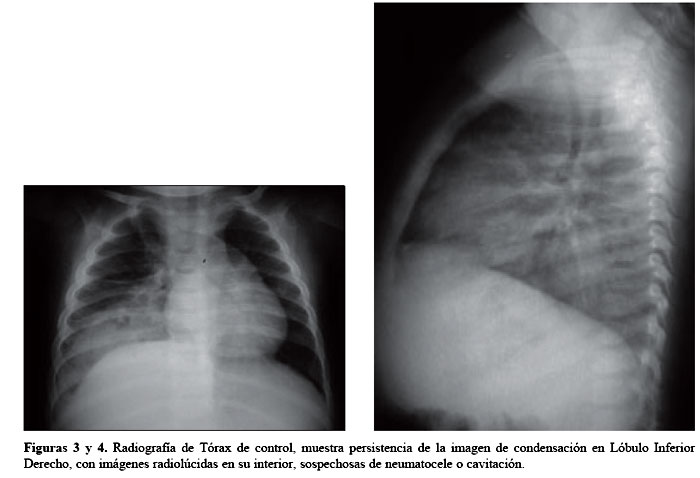

El control de sus exámenes seis semanas después de realizado el diagnóstico de neumonía atípica, los padres llegaron refiriendo que el paciente, presentaba tos escasa desde hace una semana, sin fiebre ni dificultad respiratoria. En la Radiografía de Tórax persistía la imagen de condensación en el Lóbulo Inferior Derecho. Por lo cual se le refiere a un Neumólogo, dejando cita posterior en consulta externa para seguimiento de caso. El paciente fue evaluado al día siguiente por la especialidad referida, se le solicitaron nuevos controles de Radiografías de tórax, en donde se mostraba una imagen sin cambios significativos con respecto a las placas anteriores (figura 3 y 4), por lo que se solicitó una TAC para descartar una malformación pulmonar. Las imágenes fueron informadas por Radiología como altamente sugerentes de secuestro pulmonar, por la presencia de un vaso anómalo proveniente de la Aorta diafragmática (figuras 5 y 6).

El estudio de esta patología está orientado a tener la certeza diagnóstica y a determinar la arteria aberrante que irriga la malformación, para facilitar el manejo quirúrgico. La radiografía de tórax habitualmente no es específica y muestra una imagen de condensación con bordes pocos definidos, que puede simular una neumonía o cavitación, o una masa de tejidos blandos con bordes irregularmente definidos3,4,6. Como método diagnóstico de elección se prefiere la TAC, la cual muestra una masa, habitualmente en los segmentos medio-basal (S7) o postero-basal (S10) del Lóbulo Inferior Izquierdo, que puede tener imágenes quísticas en su interior1,4,7,8. La identificación preoperatoria de la arteria aberrante es muy importante para evitar morbimortalidad durante la cirugía, utilizándose Angio-TAC o Angio-RNM como métodos de elección para este propósito, los cuales han logrado evitar el uso de técnicas invasivas como la angiografía1,47.